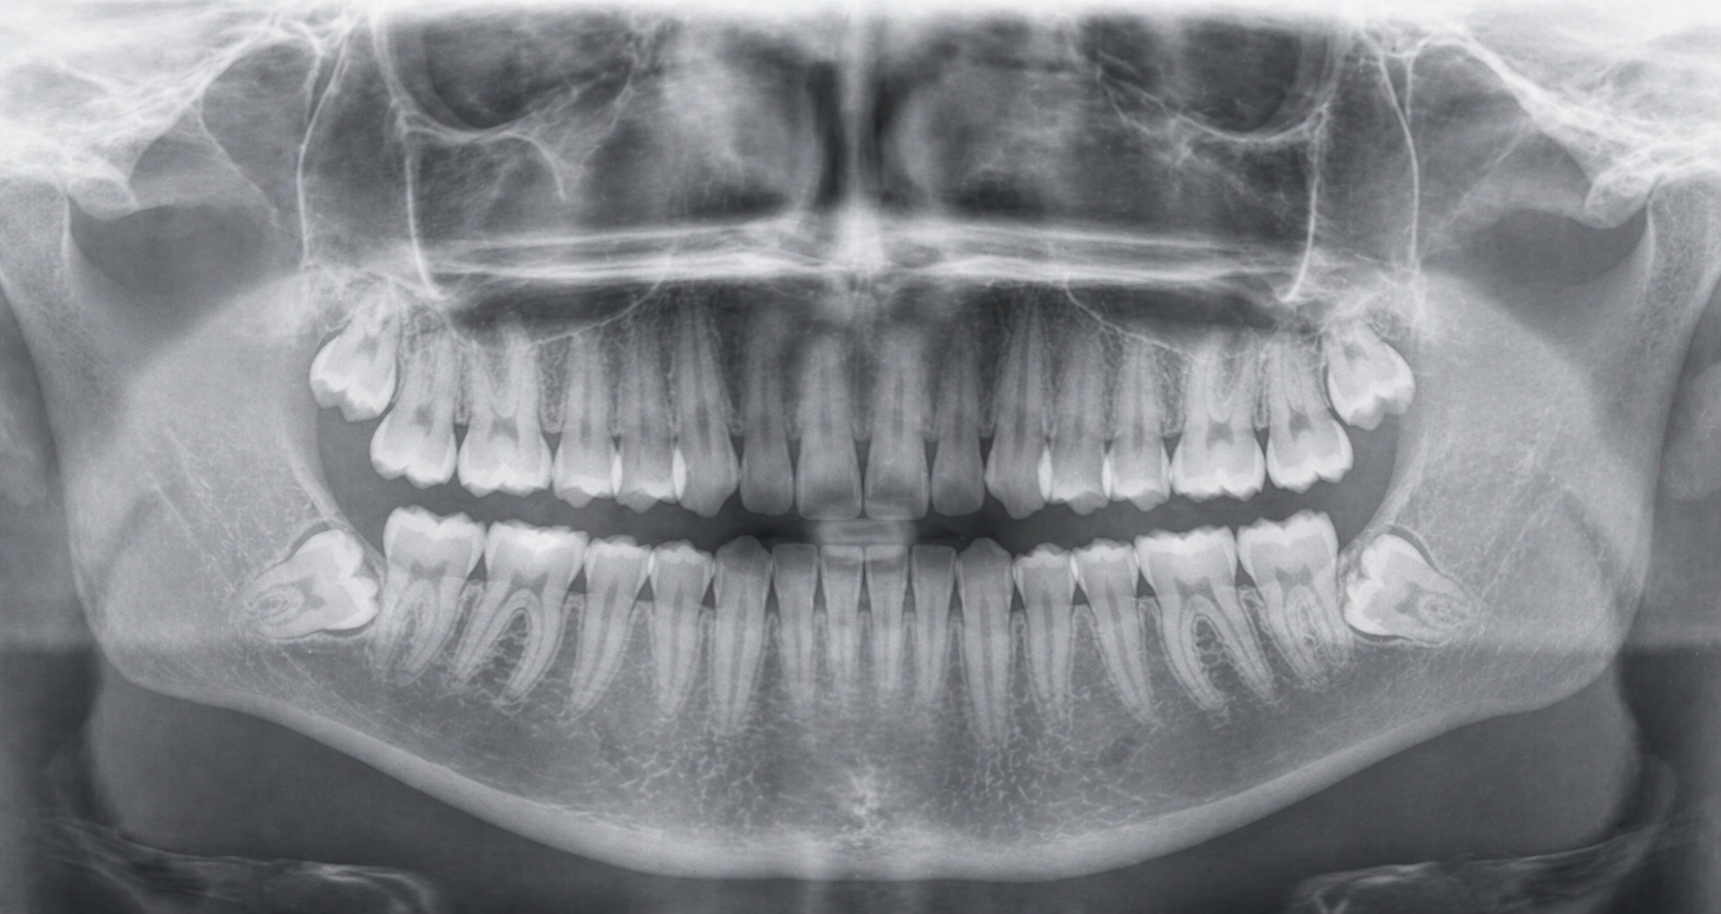

Queixals del seny inclosos o mal posicionats

Extracció dels queixals del seny

Dents inclosos o parcialment erupcionades.